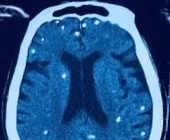

Người bệnh được chuyển lên từ tuyến trước vì rối loạn ý thức đe dọa suy hô hấp, hình ảnh cắt lớp vi tính sọ não và X-quang ngực cho thấy rất nhiều nốt cản quang trong nhu mô não và dưới da vùng ngực-bụng.